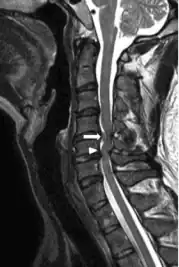

Image indicates C5–C6 with severe spinal cord compression (and large disc herniation at C4–C5 )